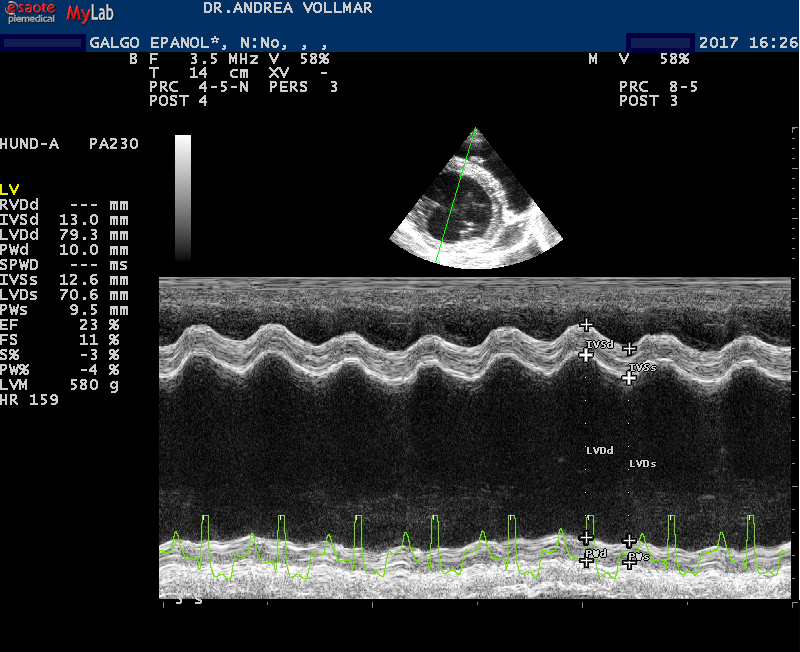

Dilatativen Kardiomyopathie (DCM)

Bei der dilatativen Kardiomyopathie (DCM) ist die Herangehensweise anders als bei MI. Die DCM tritt bei vielen größeren Hunderassen als Erberkrankung auf und unterscheidet sich bei verschiedenen Hunderassen in vielerlei Hinsicht, so auch im klinischen Erscheinungsbild und im Verlauf. Als auskultatorisch hinweisende Befunde kommen bei einigen Rassen zwar früh im Krankheitsverlauf Arrhythmien in Form von Extrasystolen oder Vorhofflimmern vor, häufig ist die Auskultation aber unauffällig. Leise Herzgeräusche entstehen erst spät im Krankheitsverlauf mit Entwicklung einer sekundären AV-Klappeninsuffizienz durch Dilatation des Anulus fibrosus und Papillarmuskelatrophie Daher basiert die Früherkennung allein auf der echokardiografischen Untersuchung, je nach Rasse ergänzt durch EKG-Befunde bis hin zum 24-Stunden Holter-EKG.

Besonders betroffene Rassen wie Dobermänner, Deutsche Doggen, Irische Wolfshunde, sollten ab dem jungen Erwachsenenalter regelmäßig kardiologisch untersucht werden - nicht nur aus zuchthygienischen Gründen, sondern auch, um dem Individuum möglichst lange eine gute Lebensqualität zu ermöglichen und die Lebenserwartung zu verbessern. Wie Erfahrungen aus der Humanmedizin und inzwischen mehrere veterinärmedizinische Studien zeigen, muss das vorrangige Ziel sein, die Erkrankung möglichst früh im präklinischen Stadium zu diagnostizieren und eine frühzeitige Therapie zu beginnen.